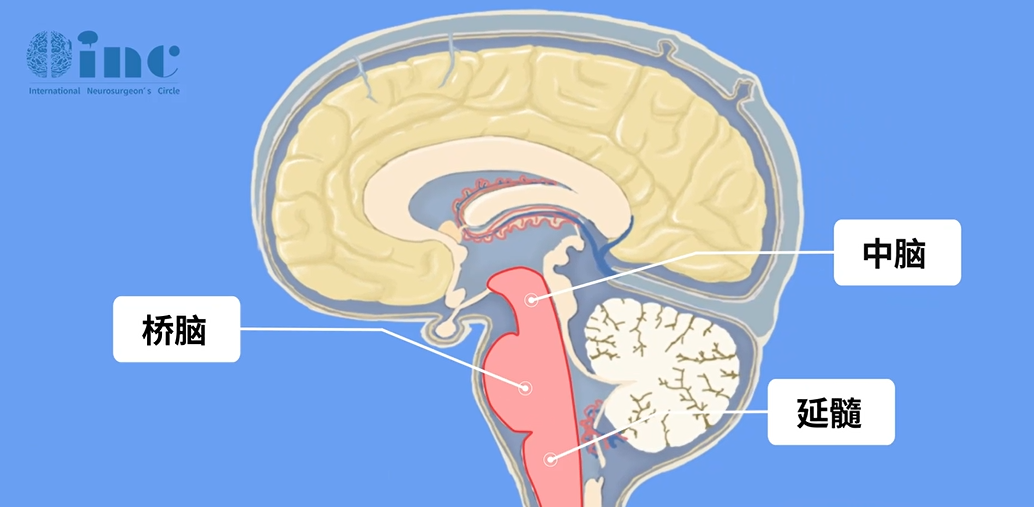

11岁的脑干室管膜瘤患儿,在一次肿瘤切除术后心跳骤停,不幸离世。医生告知,孩子是由于脑干室管膜瘤部分切除术后并发出血,引起中枢性呼吸循环功能衰竭而死亡。 这样的悲剧不在少数,...